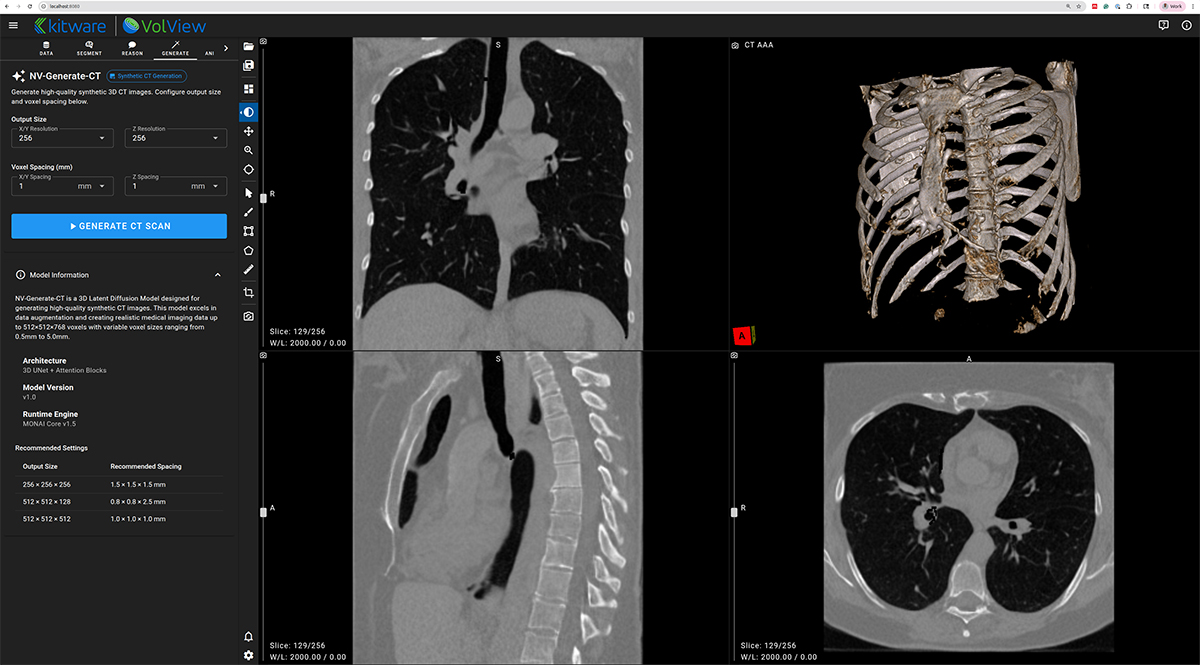

NV-Generate-CT/MR — 3D Synthetic CT and MR Generation

NV-Generate introduces the capability to generate realistic, anatomically consistent synthetic CT and MR volumes. In VolView, NV-Generate supports use cases such as data augmentation, educational content creation, and prototyping scenarios where non-protected health information (PHI) synthetic data is essential.

Learn more in the published work:

[2] https://arxiv.org/html/2409.11169v1